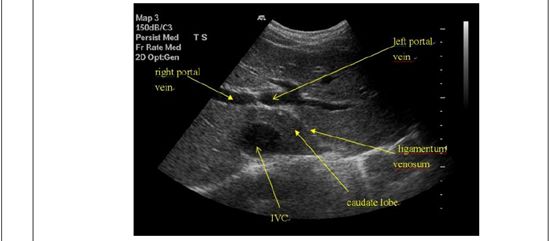

69.下圖為肝臟之橫切面,箭號所指為肝臟的那一個部位?